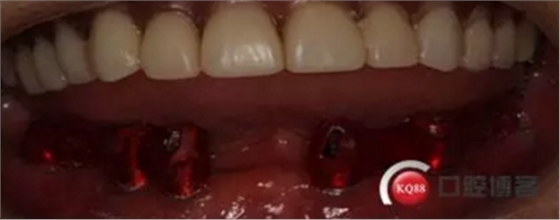

2)術前準備及手術過程,測量血壓及血糖,簽種植知情同意書;嚴格遵循無菌操作,局麻下采用微創(chuàng)技術于323436分別植入osstem4.0X10,4.0X10,4.5X7; 434446分別植入osstem4.0X1O,4.0X10,4.5X7.初期穩(wěn)定性均達到了35N.CM以上;嚴密縫合,止血,種植體位點和方向與設計一致。

4)三個月后行種植二期手術并拔除33殘冠,于34364346種植體接入成品基臺,調改活動義齒做一個改良式的套筒冠覆蓋義齒。

5)患者過渡使用2個月,待33牙槽窩和種植體周圍軟組織愈合后制取最終印模,及結合臨時修復體確定咬合關系并記錄